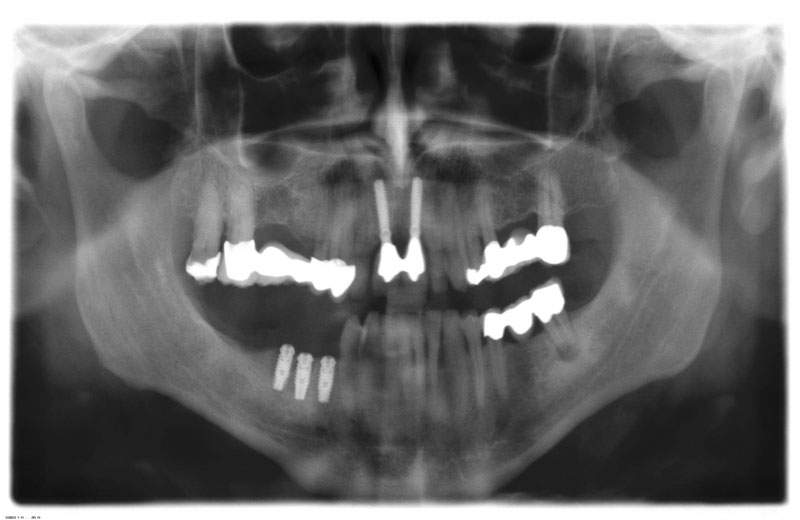

DVT mit 3D-Planung